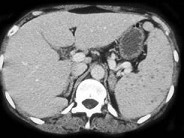

- 单项选择题骨髓移植患者发热,结合图像, 最可能的诊断为 ( )

A、脾念珠菌病

B、脾囊肿

C、肿瘤浸润脾

D、淋巴瘤

E、以上都不是